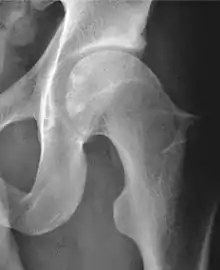

Projectional radiography ("X-ray")is often considered first line for FAI.[10] Anterior-posterior pelvis and a lateral image of the hip in question should be attained.[10] A 45-degree Dunn view is also recommended.[10][19]

Alpha angle | ![]() |

Degree of bulging of the femoral head-neck junction: In normal conditions there is a symmetric concave contour at the junction of the femoral head and neck. Loss of this concavity or bone bulging may lead to cam type impingement. The degree of this deformity can be measured by the alpha angle. Although it can be measured in the cross-lateral view, the 45° Dunn view is considered more sensitive and the frog leg view more specific in determining pathologic values. |

|